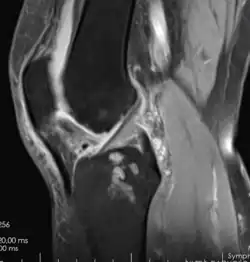

Otra técnica imagenológica útil para la confirmación diagnóstica de ésta patología es la ecografía ya que permite ver el cartílago de cualquier articulación de las extremidades (en este caso de la rodilla).[11]

Esta técnica en particular, se presenta como la técnica con mayor sensibilidad y especificidad en artrosis dado que muestra los tejidos blandos como el cartílago tanto como los tejidos óseos. Permite detectar cambios degenerativos precoces y complicaciones periarticulares y óseas, como la presencia de osteofitos, el adelgazamiento del cartílago hialino y edema subcondral, siendo particularmente útil cuando no hay certeza diagnóstica. Desgraciadamente, en el sector público no es muy utilizada debido a su alto costo y poca accesibilidad.[8]